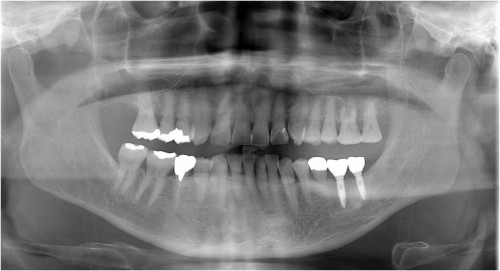

インプラント 右上4567 川口で精密インプラントなら さかえ歯科